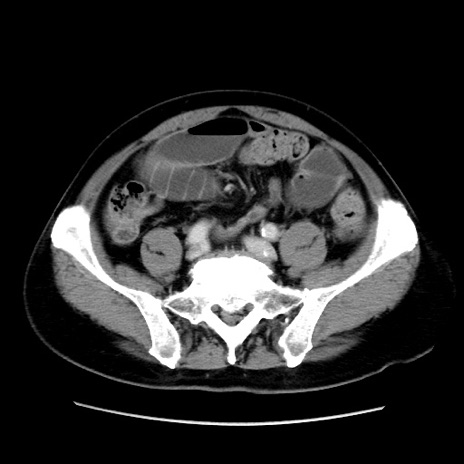

症例16(横断像)

【症例】 70歳代男性

【主訴】 腹痛、嘔吐

【現病歴】 約1ヶ月前より間欠的に腹痛と嘔吐あり、当院消化器内科を受診したところCTで多発する肝臓のLDAを指摘され、精査中であった。以降は消化器症状は安定していたが、2日前より嘔気と腹痛があり、同日より排便・排ガスが消失した。改善認めず、 本日、救急外来を受診した。

【既往歴】 大腸ポリープ切除後。

【身体所見】意識清明・会話良好、BT 36.3℃、BP 127/80mmHg、 P 80bpm、腹部:膨満あり、平坦・軟、上腹部正中および下腹部正中に圧痛あり、反跳痛なし、筋性防御なし。

【データ】WBC 7200、CRP 0.77